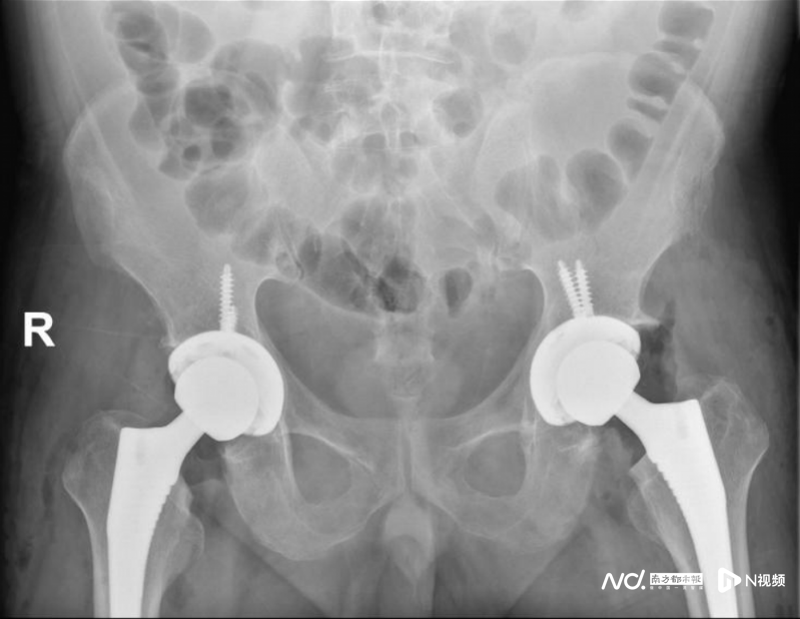

據(jù)接診醫(yī)師,醫(yī)院骨科李輝介紹,因沈先生同時(shí)患有高血壓3級(極高危)、竇性心動過速、高脂血癥、高尿酸血癥,并且因?yàn)殚L期使用激素導(dǎo)致庫欣綜合征,病情較為復(fù)雜,醫(yī)務(wù)處組織了院內(nèi)多學(xué)科專家會診,為沈生制定了詳細(xì)的治療及手術(shù)方案。在病情穩(wěn)定后,為沈先生順利進(jìn)行了雙側(cè)人工全髖關(guān)節(jié)置換。術(shù)后,護(hù)理人員和康復(fù)科給予他精心的護(hù)理及功能康復(fù)鍛煉。沈先生康復(fù)良好,在能自主行走后出院。出院后,沈先生在醫(yī)生的指導(dǎo)下堅(jiān)持康復(fù)鍛煉。近日,他給醫(yī)生發(fā)來大步流星走路的視頻,對治療效果表示非常滿意。